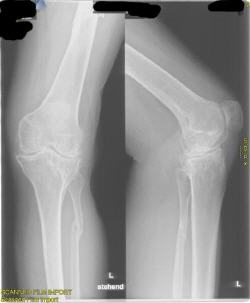

schwere X-Bein-Fehlstellung und Instabilität bei massiver Kniegelenksarthrose